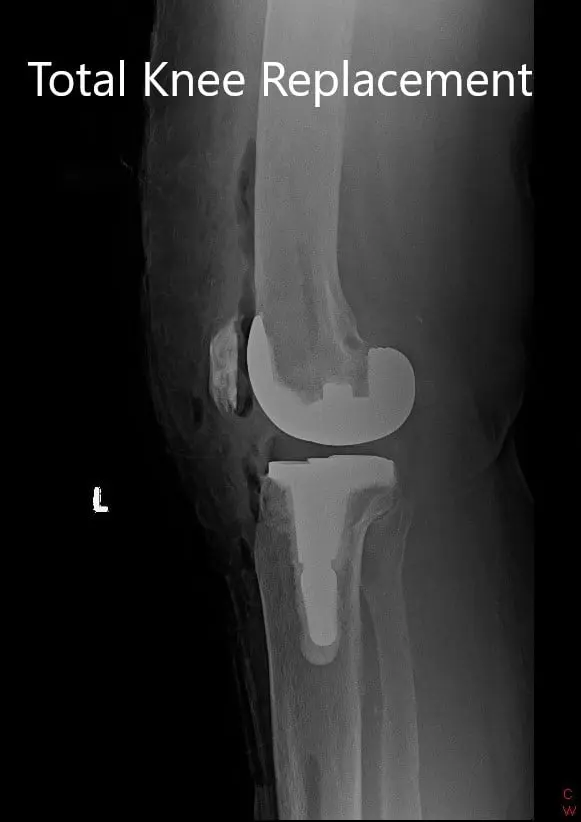

Postoperative X-ray showing the left knee joint with prosthesis in anteroposterior and lateral views

The patient had a good recovery post-op with stable vitals. He was able to walk with support the same day of the surgery. His calves were soft and non-tender with Homan sign negative. The pain was well controlled with medications.

Twelve weeks post-op, he was walking without any support totally pain-free. He had a full range of motion and continued a home exercise program. He was back at his job and expressed satisfaction with the outcome. He reported decreased pain in the right knee secondary to offloading.